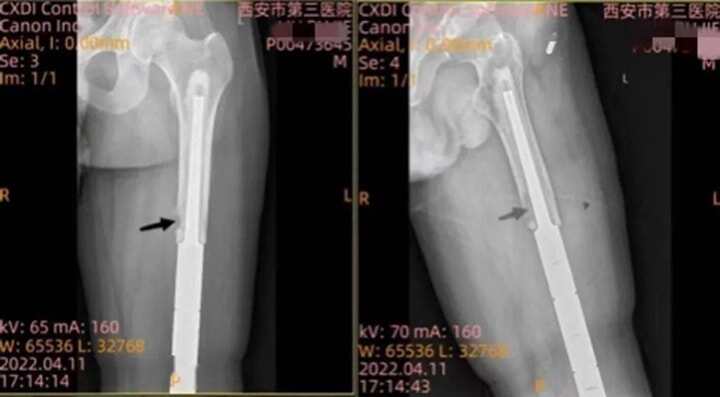

國內首例3D打印“瓦片”保住肢體 做別人不敢想的事

行業(yè)資訊 1279天前

國內首例3D打印“瓦片”保住肢體